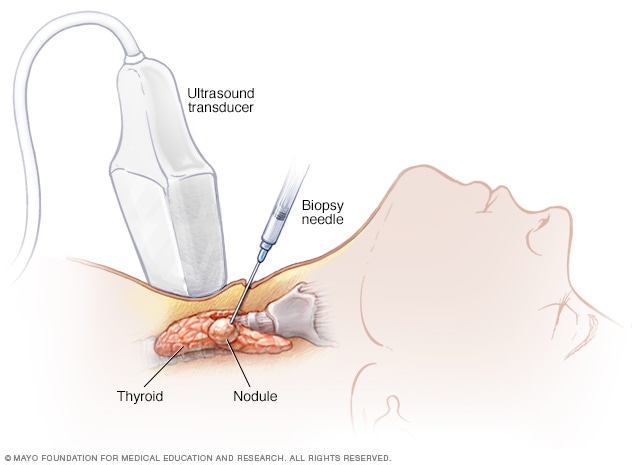

Thyroid Cancer Explore vol.3 no.2(2201 「Thyroid Cancer Expl Thyroid Cancer Treatment (PDQ®) - NCIの詳細情報

Thyroid Cancer Treatment (PDQ®) - NCI。Comparative Analysis of Metastatic Thyroid Carcinoma versus。The Role of Positron Emission Tomography/Computed Tomography。

ThyroidCancerExploreVol.3No

「ThyroidCancerExpl